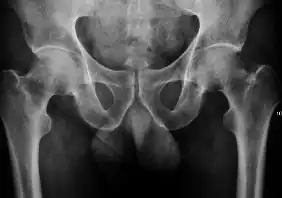

Projectional radiography ("X-ray") is the first imaging technique of choice in hip pain, not only in older people with suspected osteoarthritis but also in young people without any such suspicion. In this case plain radiography allows categorization as normal hip or dysplastic hip, or with impingement signs, pincer, cam, or a combination of both.[1]

X-Ray

Projectional radiography ("X-ray") is currently useful not only in older people in whom osteoarthritis of the hip is suspected but also in younger people without osteoarthritis, who are being evaluated for femoroacetabular impingement (FAI) or hip dysplasia.[1]

Plain radiography allows us to categorize the hip as normal or dysplastic or with impingement signs (pincer, cam, or a combination of both). Besides these, pathologic processes like osteoarthritis, inflammatory diseases, infection, or tumors can also be identified (Figure 1).[1]